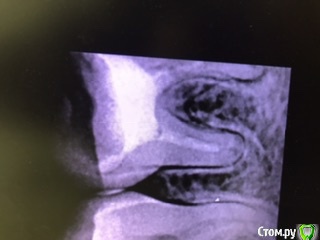

В середине марта обратилась на перелечивание каналов с гранулемой в 46 зубе.

Прикрепляю рентген до, 3 рентгена после первого лечения, рентген после установки гуттаперчевых штифтов. Также есть КТ до перелечивания, вдруг кто-то заинтересуется.